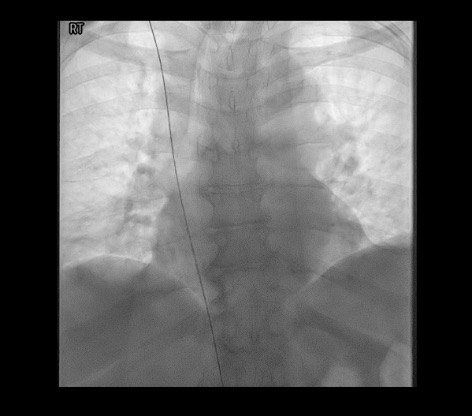

View wire to IVC

Fluoroscopy showing wire passed to IVC confirming venous position